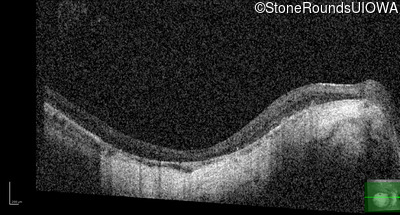

Optical Coherence Tomography - Left - 20/100 -1

Exemplar / OCT Stack

OCT Stack